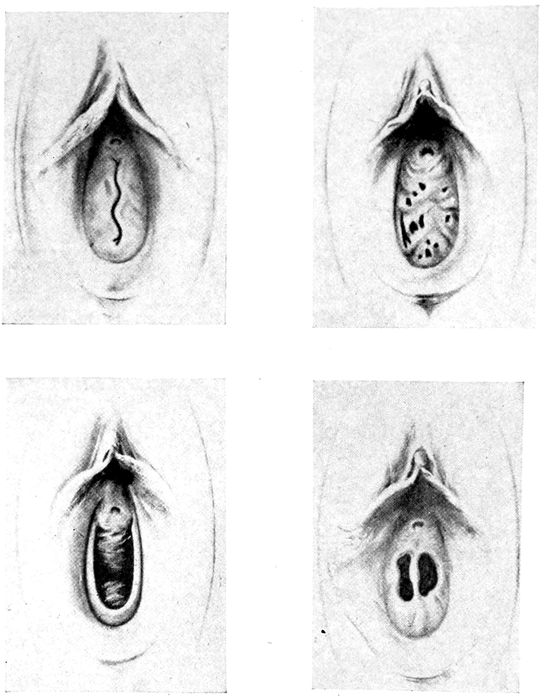

Fig. 7 B.—Varieties of hymen. (American Text Book.)